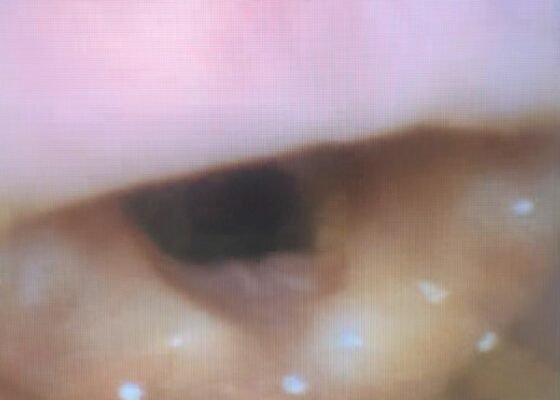

The Advantage of Using Video Laryngoscope in Puncture and Incisional Drainage of Peritonsillar Abscess: A Case Report

DOI: https://doi.org/10.21980/J8G935Incision of the peritonsillar abscess was performed with the assistance of the C-MAC video laryngoscope which provided a clear, illuminated, and unobstructed view of the incision site. Local anesthesia with 1% xylocaine was administered, and the abscess was incised with a scalpel and drained with a forceps.